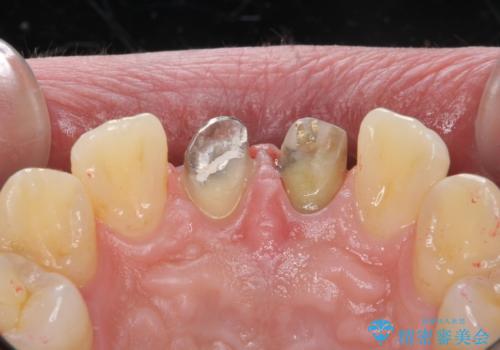

- 前歯のかぶせ物の変色を主訴に来院された患者様です。

根管治療からのやり直しはご希望されませんでした。

今回はe-maxクラウンで修復していきます。